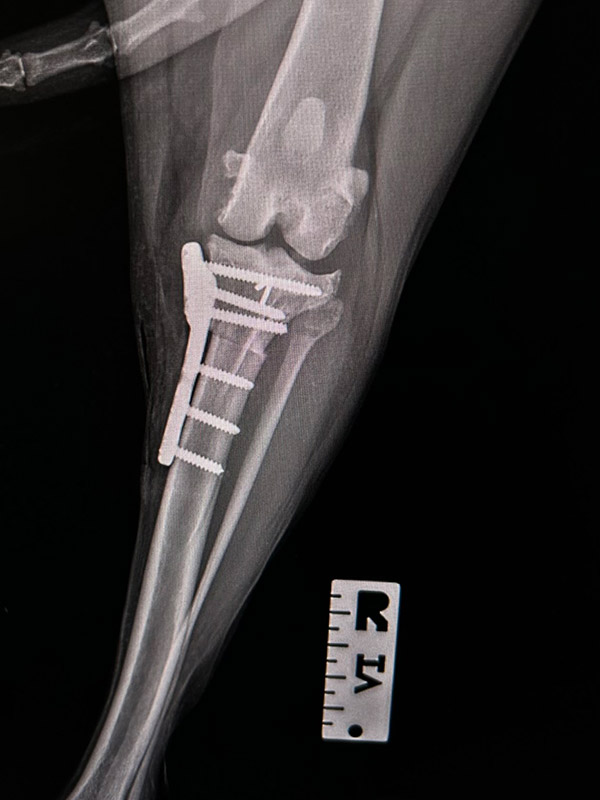

(Tibial Plateau Leveling Osteotomy)Niestabilność w stawie udowo-piszczelowym charakteryzuje występowanie znacznego dyskomfortu oraz wysokiego stopnia kulawizny i prowadzi do szeregu zmian degeneratywnych w stawie, uszkodzenia chrząstek stawowych, łąkotek, a także powstawania odczynów wytwórczych ograniczających ruchomość w stawie prowadząc do jego ankylozy.

TPLO poprzez modyfikację geometrii kąta nachylenia płaszczyzny stawowej kości piszczelowej przy jej wysokim nachyleniu pozwala na uzyskanie stabilności w stawie udowo-piszczelowym.